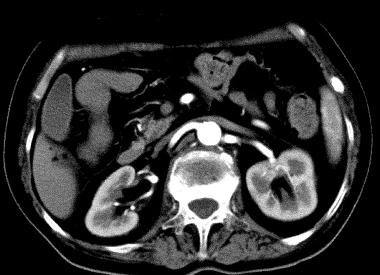

Фото: снимок КТ почек с контрастом

Болюсное усиление – это капельное введение контраста на протяжении всего исследования. Контрастное вещество медленно поступает в почку и «захватывается» патологическими клетками. В результате накопленный в пораженной области радионуклид делает границы этой области хорошо различимыми на снимках.